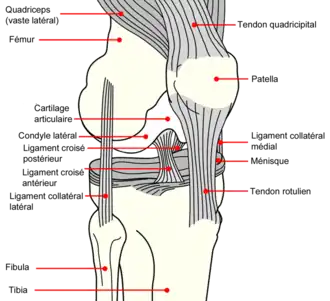

Éléments d'anatomie du genou

Le genou naturel est composé de trois parties osseuses :

- l’extrémité inférieure du fémur qui a la forme de deux roues accolées : les condyles ;

- l’extrémité supérieure du tibia, encore appelé plateau tibial ;

- la patella (ou rotule) : petit bouclier situé sur l’avant du fémur.

À ceci s'ajoutent d'autres éléments, favorisant le fonctionnement parfois très contraignant de l'articulation (voir schéma) :

- Une couche de cartilage recouvrant chaque partie osseuse en regard d'une autre : condyles fémoraux, partie antérieure du fémur, face postérieure de la patella et plateau tibial.

- Deux petits coussins de cartilage fibreux, les ménisques, disposés entre le fémur et le tibia. En forme de croissant mobile — seules les cornes s'insèrent sur le plateau tibial —, ils augmentent la congruence articulaire et amortissent le contact entre le cartilage du fémur et celui du tibia. Ils sont situés l'un vers l’intérieur (ménisque médial ou interne, qui répond au condyle médial du fémur) et l'autre vers l’extérieur du genou (ménisque latéral ou externe, en regard du condyle latéral).

- Des ligaments assurant la stabilité de l’articulation, et dont les principaux sont :

- deux ligaments croisés :

- le ligament croisé antérieur (LCA) — ligament croisé antéro-externe (LCAE), dans l'ancienne nomenclature —, son origine se trouve sur la surface pré-spinale de l'espace intercondylaire du plateau tibial, entre les cornes méniscales. Il se dirige en haut, en arrière et en dehors pour venir s'insérer sur la surface intercondylienne du condyle fémoral latéral. Le LCA croise en dehors le :

- ligament croisé postérieur (LCP) — ou ligament croisé postéro-interne (LCPI) de l'ancienne nomenclature —, de son origine, sur la surface rétrospinale de l'aire intercondylaire, il se dirige en haut, un peu en avant et en dedans, pour s'insérer sur la surface intercondylienne du condyle fémoral médial.

- Deux ligaments collatéraux : ligament collatéral tibial (ou interne) et ligament collatéral fibulaire (ou externe) maintenant le genou en dedans et en dehors. Les ligaments collatéraux sont également croisés, permettant une bonne stabilité du genou.

- Les ligaments maintenant la patella : le tendon patellaire (rotulien), reliant la patella au tibia et les tendons du muscle quadriceps reliant la patella à la cuisse. Ils assurent la transmission de la traction du quadriceps sur le tibia même en position de forte flexion du genou, la patella agissant comme poulie.

- Une capsule articulaire contenant le liquide synovial qui baigne l'intérieur de l’articulation et y favorise les glissements.

Schématiquement, le LCP est tendu genou fléchi, alors que le LCA est tendu quand la jambe est tendue. Ils sont soumis à de très fortes contraintes, en particulier lors des sports de stop-and-go (démarrage-arrêt) — comme le tennis ou le squash — et de pivot — le football, le ski, le judo… —, ainsi que lors d'activités nécessitant une position à genoux ou accroupie ou dans certains travaux de force.